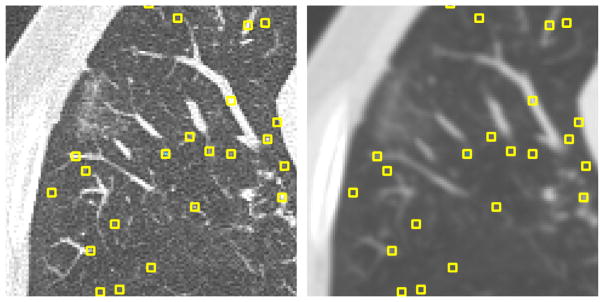

To automatically generate POIs, we first computed the 3D local maxima on a blurred version of each scan. Blurring was done on each axial slice using a Gaussian kernel with a scale of 1.0 mm (see Fig. 1). To prevent points from being too close to each other, the list of initial points was pruned. First, the points were sorted by density in descending order. Starting from the top of the list, moving downwards, all points within distance of five voxels to a point higher on the list were removed. As the majority of points selected in this way turn out to be vessels, an equal number of randomly generated points at least five voxels from any other point were then added to the list of POIs. For each scan, four axial sections along the z-axis direction were filled with POIs in this way. In each scan, we have selected sections which are approximately evenly distributed in the z-axis and which contain a large proportion of lung tissue. Fig. 2 illustrates the location of the four sections in which POIs have been generated from two scans.

Fig. 1.

(Left) Original axial section from scan 01; (Right) same slice after blurring, overlaid with automatically generated POIs. The POIs are local maxima, sorted by intensity and pruned to be further than five voxels apart. Squares in the figure have been magnified for illustration purpose.